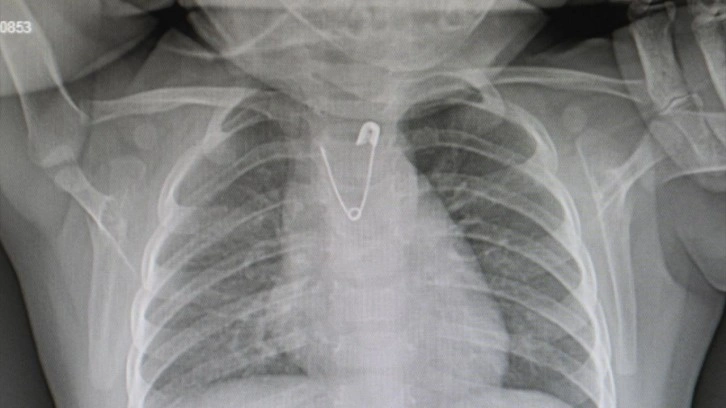

Ankara'da yakasına takılı olan çengelli iğneyi ucu açık şekilde yutan 10 aylık küçük kız, Ankara Eğitim ve Araştırma Hastanesine getirildi. Çengelli iğnenin alındığı operasyon sonrası Ankara Eğitim ve Araştırma Hastanesi Çocuk Cerrahisi Uzmanı Doç. Dr. Doğuş Çalışkan, ebeveynlere uyarılarda bulundu.